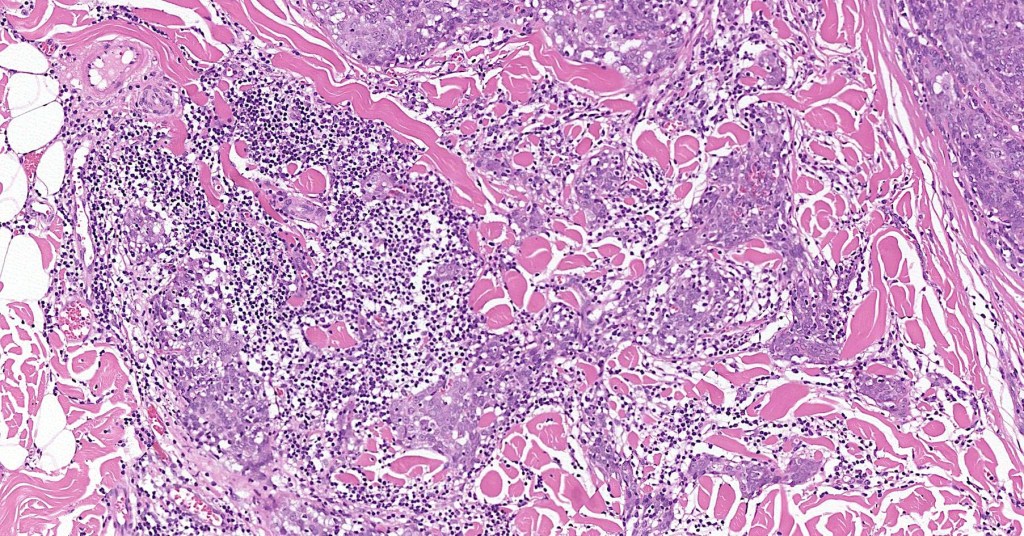

•Dermal generally circumscribed tumor nodule (less often it may show an infiltrative border)

•Syncytial epithelial component in nests, cords or sheets surrounded by an intense lymphoplasmacytic infiltrate

•Epithelial cells are large with abundant cytoplasm and vesicular nuclei with conspicuous nucleoli

•Marked mitotic activity, variable pleomorphism

•Absence of an epidermal connection